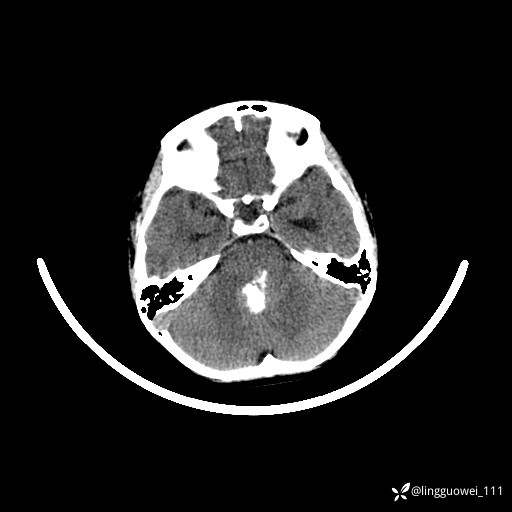

男,8岁,外伤后发现颅内占位,定位定性,4天后公布结果。

患者性别:男

患者年龄:8岁。

主诉:外伤后发现颅内占位。

外院做的手术,术后回本院复查,只有平扫,定位在哪?良性还是恶性?